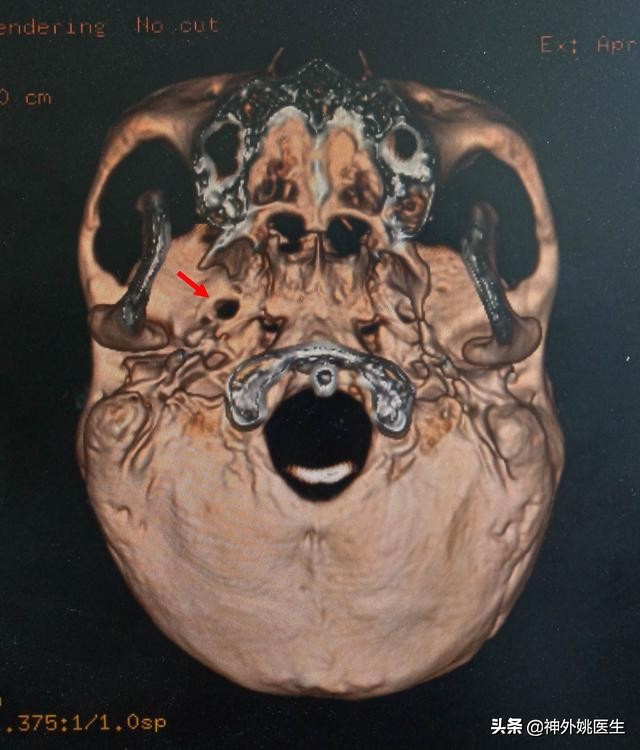

头CT检查:(图1、2)

图2 卵圆孔形态规则,宽大(红色箭头所示)。